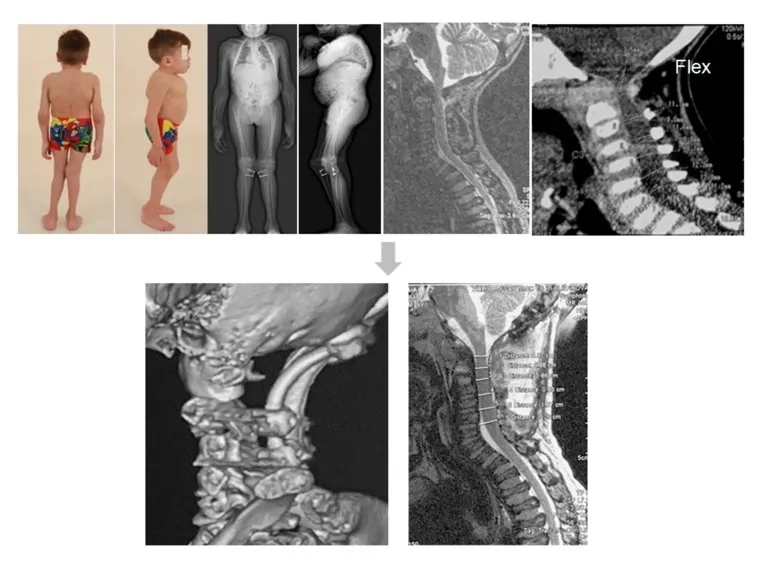

Результаты лечения пациента с мукаполисахаридозом в Центре им. Илизарова

Фото: фото: пресс-служба Центра им. Илизарова

У пациентов с наследственной патологией нередко отмечаются ортопедические проблемы со стороны позвоночника и конечностей. При патологии позвоночника чаще встречаются сколиотические деформации, кифотические и их сочетание — кифосколиотические деформации. На уровне верхнешейного отдела позвоночника отмечается нестабильность (патологическое смещение позвонков), учитывая особенности строения связочного аппарата. Полина Вячеславовна вспомнила случай, когда консультировала пациентов в одной из казвказских республик. На осмотр принесли ребенка с нарушением функции тазовых органов, отсутствием активных движений и чувствительности в нижних конечностях, возникшие при резком наклоне головы во время визита к парикмахеру. «На лицо были все признаки генетического заболевания. По данным МРТ исследования головного мозга и краниовертебрального перехода (верхнешейного отдела позвоночника) отмечались признаки нестабильности. По срочным показаниям пациент был доставлен в Центр Илизарова, где ему было проведено оперативное лечение. На 2-3 сутки отмечалась положительная динамика в виде восстановления чувствительности в конечностях, появились активные движения в них. При выписке из клиник пациент вышел на своих ногах. Так же у ребенка наблюдалась кифотическая деформация на уровне грудопоясничного перехода. Через полгода он к нам приехал на второй этап лечения», — говорит врач.